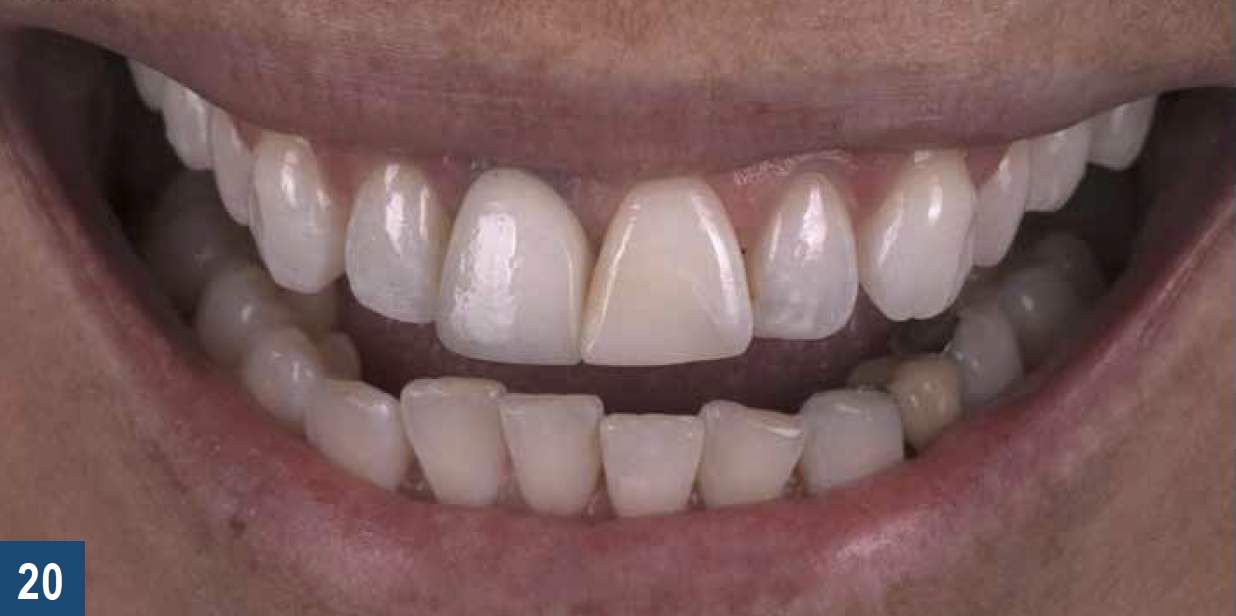

Patients often seek replacement of their existing anterior restorations for cosmetic reasons (Figure 20), and they may not always be aware of the impact that whitening their natural teeth can have on the overall esthetics of their new smile. These situations represent an excellent opportunity for the clinical team to inform their patients about the use of custom-fit trays for at-home teeth bleaching. Prior to the restorative treatment, it is important to ensure that the patient understands that the shade of their new ceramic crowns or veneers will not lighten in color if teeth-bleaching products are used after the definitive restorations have been placed. It is equally important for patients to understand that ceramic will not be affected by extrinsic stains and aging in the same way as the adjacent dentition,53 and each restoration will serve as the benchmark shade value that will alert them that their natural teeth have discolored. Consequently, some maintenance will be required in the form of periodic or ongoing teeth-bleaching treatment to maintain the uniformity of tooth shade.

Fig 20. Pretreatment situation for a patient requesting cosmetic improvement of a pre-existing implant crown (tooth No. 8) and composite resin build-up for a fractured natural incisor (tooth No. 9).

Figure 20